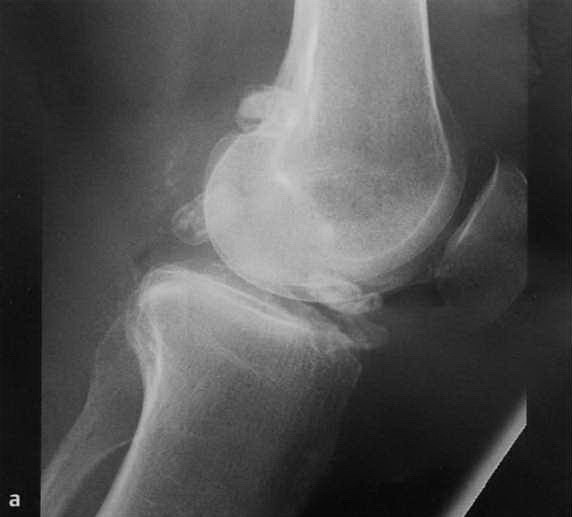

а-d Хондроматоз коленного сустава . Пациент 57 лет с рецидивирующим выпотом в коленном суставе: а, b) Рентгенологическое исследование в двух проекциях: множественные поражения в межмыщелковой и задней части коленного сустава.

с) Сагиттальная проекция в Т1 -взвешенной последовательности. Синовиальный хондроматоз с гипоинтенсивным сигналом;

d) Гипоинтенсивный синовиальный хондроматоз в межмыщелковой области